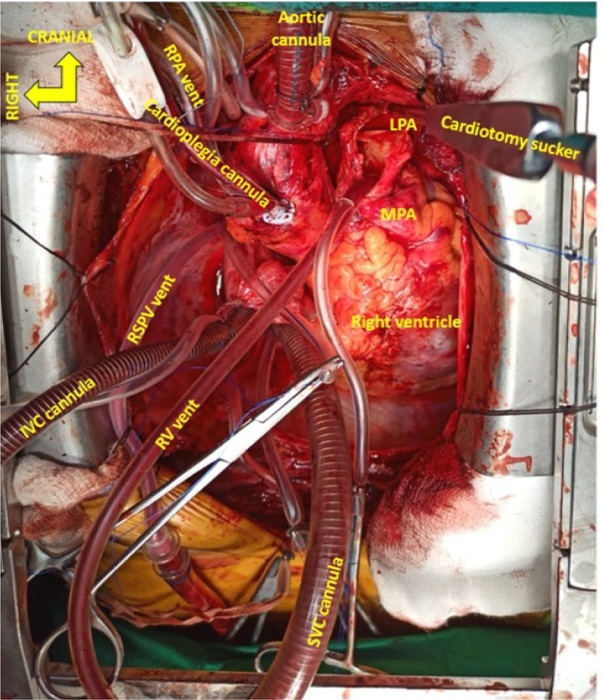

Standard CPB circuit with St. Thomas II cardioplegia on standby and a cell saver (C.A.T.S®, Fresenius Kabi) is established. An aortic cannula and two straight venous cannulae for bicaval cannulation of appropriate size are used. Four pump suction lines are readied for a free cardiotomy sucker, vent sucker of the right superior pulmonary vein (RSPV), right ventricle, and either of the PAs (Figures 1 and 2). A hemoconcentrator for ultrafiltration is connected to the bypass circuit to achieve negative fluid balance. Core temperature is decreased to 32-34 °C (mild hypothermia), and flows are maintained at 2 to 2.4 l/min/m2. A high-pressure external sucker attached to the cell saver is used to connect an olive tip sucker, which is used as a dissector. The α-stat strategy of pH management is employed.

The operation is performed via a median sternotomy. After an inverted T pericardiotomy and attachment to the wound edges, direct pressure manometry by puncturing MPA is done. The superior vena cava (SVC) is looped and mobilized by cautery dissection. Mobilization of the branch PA is done intrapericardially, and none of the pleurae are opened. The aorta is looped with a vessel loop for better visualization (Figures 1 and 2).

A vent catheter is introduced into the RSPV. The left pulmonary artery (LPA) is then dissected beyond the origin of the upper lobe artery with careful preservation of the left phrenic nerve. A small arteriotomy is made in the right pulmonary artery (RPA) just right to the aorta, and a vent catheter is introduced into it and snared. Ventilation is then stopped.

With the surgeon standing on the right side of the patient, an incision is then made in the MPA and is extended into the LPA beyond the origin of the upper lobe artery. Stay sutures are taken and the arteriotomy is exposed. A sump sucker is introduced into the right ventricle via the pulmonary valve and snared through the MPA wall. If bleeding from the RPA obscure the field of view, a vascular clamp may be applied upstream to the RPA vent.